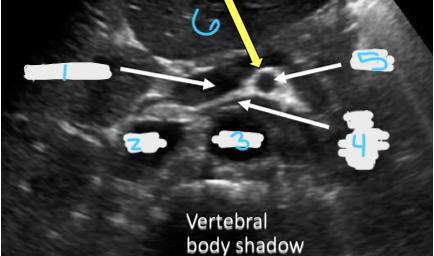

<p>In this sagittal view, what is #1?</p>

In this sagittal view, what is #1?

Splenic Vein

<p>In this sagittal view, what is #2?</p>

In this sagittal view, what is #2?

Celiac Trunk

<p>In this sagittal view, what is #3?</p>

In this sagittal view, what is #3?

SMA

<p>In this sagittal view, what is #4?</p>

In this sagittal view, what is #4?

Aorta